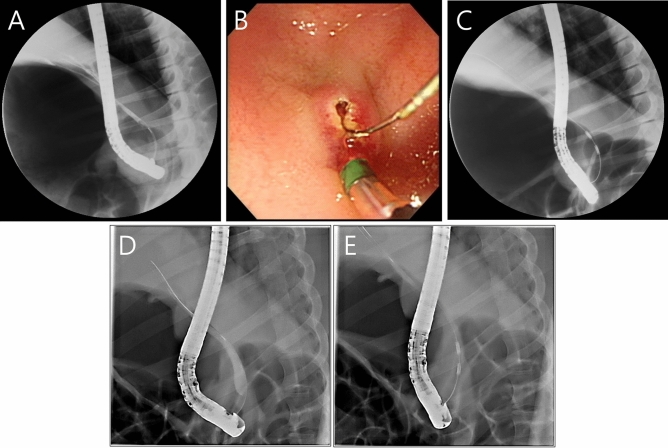

Expert biliary endoscopists (C-I. K, SI. J., and S. J.) performed endoscopic retrograde cholangiography (ERC) on the animals using a standard side-viewing duodenoscope (TJF-240; Olympus Co. Tokyo, Japan). After duodenal intubation with the scope, an endoscopic retrograde cholangiopancreatography (ERCP) sphincterotome (CleverCut3V™; Olympus Co) was inserted into the bile duct using the wire-guided cannulation technique with a 0.035-inch hydrophilic-tipped guidewire (Boston Scientific Corporation, Natick, MA, USA) to obtain a cholangiogram (Fig. 2A). Then, endoscopic biliary sphincterotomy was done (Fig. 2B) for the easy insertion of the RFA catheter and a suction technique was used to maximize contact between the mucosa of the CBD and the RFA catheter. The endobiliary RFA catheter was advanced into the distal common bile duct (CBD) over the guidewire under fluoroscopic guidance (Fig. 2C). RFA was performed with the previously mentioned settings using the suction technique (Fig. 2D,E). If the RFA catheter did not contact the mucosa of the CBD, the temperature displayed on the RFA generator did not reach the target point and the power was automatically turned off. Additional post-RFA cholangiography was performed to evaluate any immediate adverse events such as perforation or bleeding.

After endoscopic RFA application using previously reported settings, four out of 10 animals died unexpectedly (40%) between two and four weeks after the procedure. We proceeded with immediate autopsies to determine the cause of death and found that all four animals died of sepsis due to cholangitis. In the six surviving animals, ERC was obtained four weeks after the procedure to confirm the degree of BBS (Fig. 4). In one animal (No. 5), BBS was not formed, probably due to inadequate RFA application (Fig. 4D). On the ERC examination of five animals, the median length of the stricture area was 10.1 mm (7.1–12.9 mm), and the median diameter of the upstream dilation was 20.6 mm (8.1–33.8 mm) (Table 1).